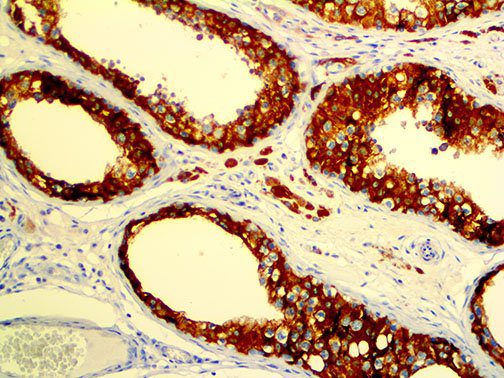

It is the ICU physician who is most likely to witness one of the deadliest manifestations of the abnormal immunological response, the cytokine storm syndrome (CSS). This response is also referred to by some as the cytokine release syndrome (CRS). CSS is characterized by continuous activation and expansion of macrophage and lymphocyte populations, which secrete large amounts of cytokines, causing the cytokine storm. This massive cytokine release is akin to hemophagocytic lymphohistiocytosis (HLH) disease, a syndrome characterized by initial unchecked and persistent activation of cytotoxic T lymphocytes and NK cells.

Clinical and laboratory manifestations of HLH include fever, enlarged liver and/or spleen, neurologic dysfunction, coagulopathy, liver dysfunction, cytopenias (i.e., low levels of erythrocytes, leukocytes, and/or platelets), hypertriglyceridemia, hyperferritinemia, hemophagocytosis, and eventually diminished NK cell activity as the immune system becomes progressively paralyzed. HLH can be familial (primary HLH) or secondary to another disease process (sHLH), such as rheumatic disease, in which it is referred to as macrophage activation syndrome (MAS, characterized by elevated ferritin).

This activation induces inflammatory monocytes to highly express IL-6, starting a localized and then systemic cascade effect that results in hyperproduction of IL-6, which accelerates the inflammatory process. Because IL-6 also increases vascular permeability, excessive levels cause blood vessels to become very leaky. This, along with clotting factors released from vascular endothelial cells, stimulates the coagulation cascade, resulting in microthrombosis (tiny clots), which leads to ischemia and tissue death of the kidney, intestines, heart, liver, brain and extremities.